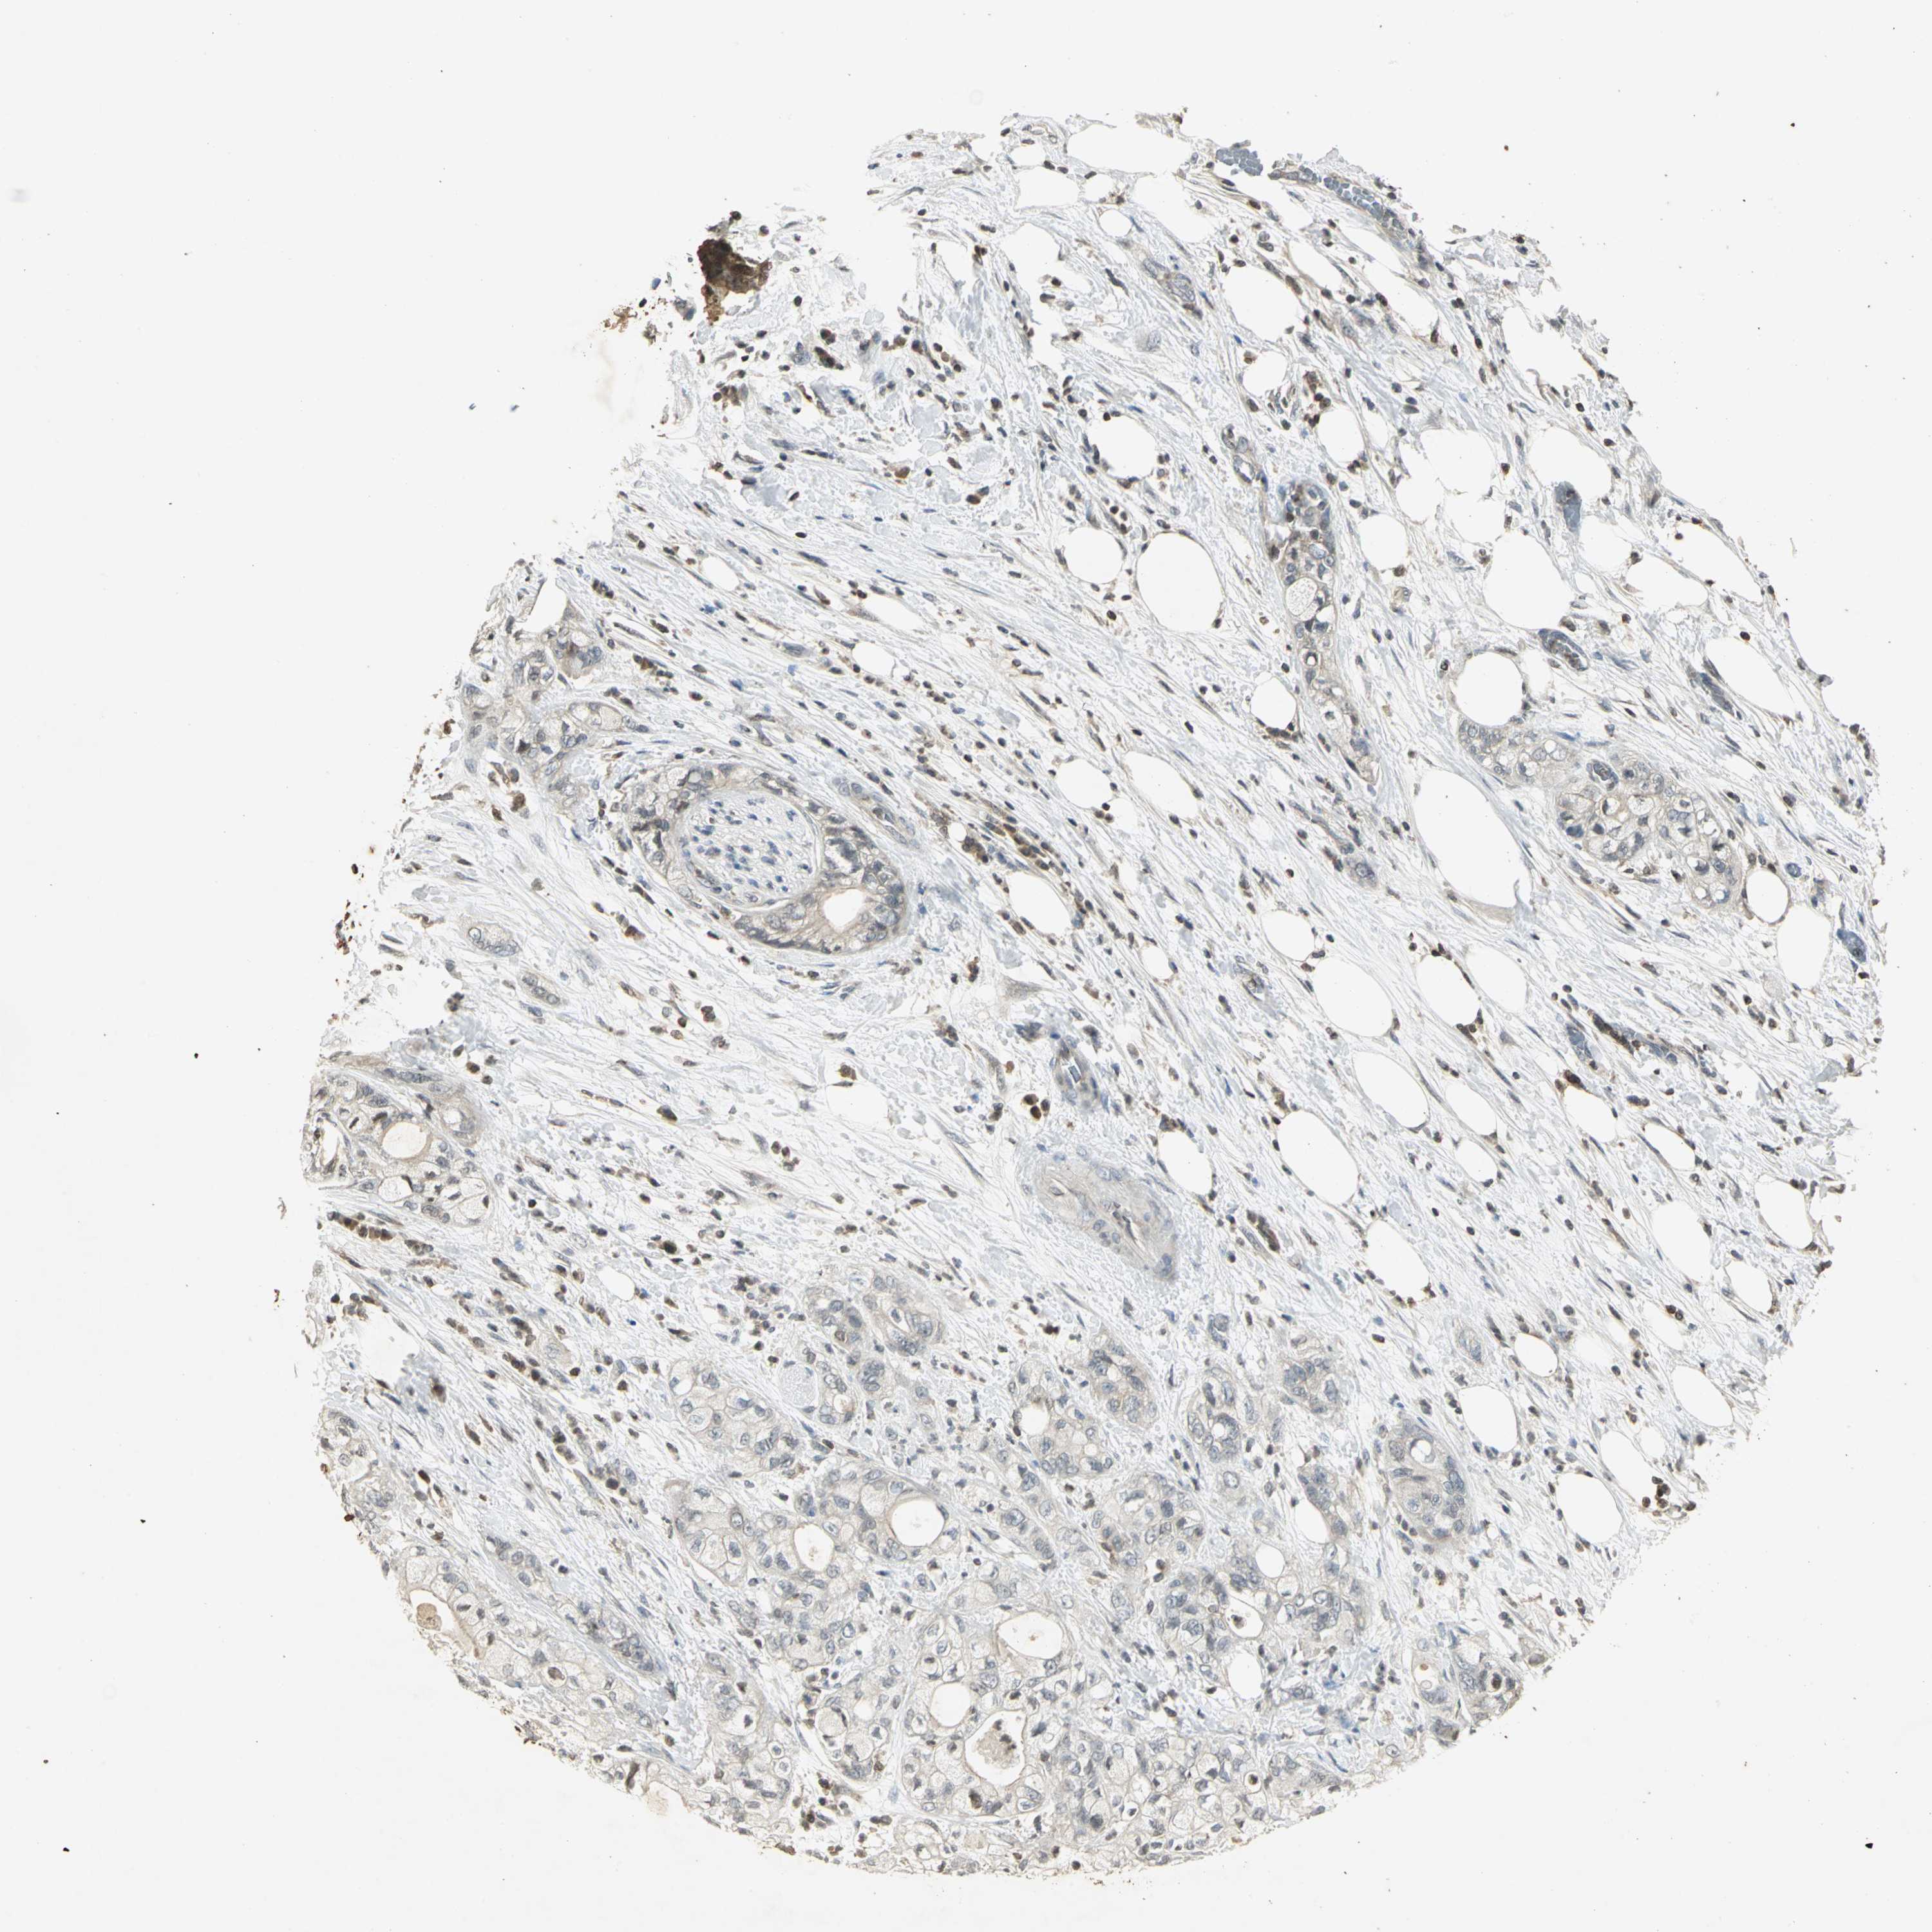

PANCREATIC CANCER - Protein expressioni

A mouse-over function shows sample information and annotation data. Click on an image to view it in a full screen mode. Samples can be filtered based on level of antibody staining by selecting one or several of the following categories: high, medium, low and not detected. The assay and annotation is described here.

Note that samples used for immunohistochemistry by the Human Protein Atlas do not correspond to samples in the TCGA dataset.

Antibody stainingi

Antibody staining in the annotated cell types in the current human tissue is reported as not detected, low, medium, or high, based on conventional immunohistochemistry profiling in selected tissues. This score is based on the combination of the staining intensity and fraction of stained cells.

Each image is clickable and will lead to virtual microscopy that enables deeper exploration of all samples and also displays staining intensity scores, fraction scores and subcellular localization as well as patient and tissue information for each sample.

Antibody HPA018467

Antibody CAB005247

Adenocarcinoma, NOS

Adenocarcinoma, metastatic, NOS